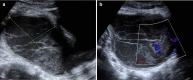

We present a case of a 14-year-old girl, Bacillus Calmette-Guérin (BCG) vaccinated, who presented with vague symptoms of abdominal pain, weight loss, and fatigue. Imaging studies revealed a pelvic mass, later found to be pelvic tuberculosis, a rare diagnosis to consider at this age. The diagnostic approach was difficult, since all investigations pointed strongly to a malignancy, from clinical, imaging (ultrasound and magnetic resonance), laboratory (elevated CA-125), and even macroscopic findings at laparotomy. Histopathology was the first hint (noncaseous granulomata), but the ultimate documentation of Mycobacterium tuberculosis relied on a persistent clinical suspicion, despite contradicting results. Surgical approach could have been mutilating, with irreversible consequences, considering it was a girl with a long reproductive life ahead. Tuberculosis is still a great masquerade, especially the extrapulmonary forms, and although infrequently seen at this age, it should thus be considered in the differential diagnosis of complex pelvic masses in order to avoid surgical iatrogeny/morbidity.